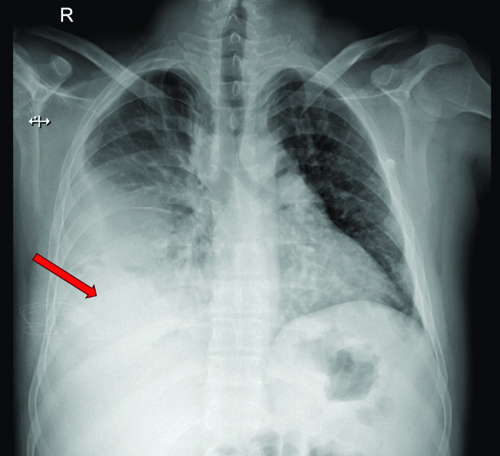

Radiological investigations included a chest X-ray showing right middle and lower zone homogeneous opacity obliterating the right cardiophrenic and costophrenic angles, suggestive of right pleural effusion [Table/Fig-2]. An ultrasound of the thorax indicated a gross right pleural effusion (>1000 cc) with internal septations. High-Resolution Computed Tomography (HRCT) and CT Pulmonary Angiogram (CTPA) confirmed the gross right pleural effusion without evidence of thromboembolism [Table/Fig-3]. It showed a large abnormal communication between the left distal ascending aorta and the right wall of the main pulmonary artery [Table/Fig-4].

Chest X-ray showing right middle and lower zone homogenous opacity (red arrow) with obliteration of the right cardiophrenic and costophrenic angles.